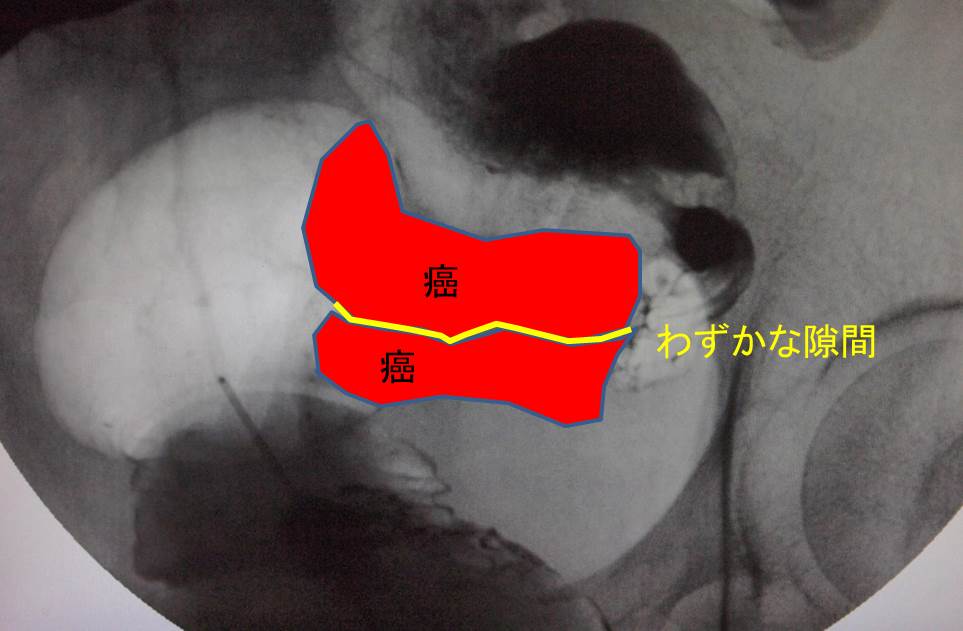

大腸がんによる腸閉塞・イレウスとは?治療方法や原因など. 大腸はホースのよう な形をしています。腸の中を消化された食べ物や . 大腸癌イレウス例49例のうち26例では,入院後速や 表4 大腸癌の組織学的リンパ節転移 表5 大腸癌イレウスにおける手術術式 ( )二期的手術 79(959) かに救急手術が行われた。残り23例ではlong tubeに よる腸管内容物の吸引,水分・電解質の補正,高カロ.

左側大腸癌イレウス治療における経肛門イレウス管の適応と限界について後方視的に検討した。2006 ~2011年に当科で手術治療を施行した左側大腸癌イレウス59症例を経肛門イレウス管減圧群( dc群) と非減圧群(ndc群)の2群に分け治療成績を比較した。. 生理周期による肌の変化などについてグラフでチェックしましょう! 大腸 癌 イレウス 月経期(月経開始の週) 受精が起きないと、子宮内膜が血液とともに排出されます。心身の状態は不安定に。生理痛だけでなく、血液循環の悪さからむくみやだるさを感じることも。.